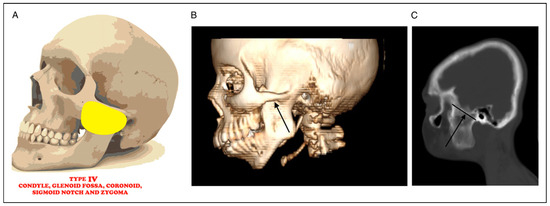

Braimah-Taiwo et al. New Classification System and Treatment Algorithm of Mandibulo-Maxillary Synostosis Related to Noma. Field Experience From Noma Children Hospital Sokoto, Nigeria

by Ramat Oyebunmi Braimah, A. O. Taiwo, H. O. Olasoji, J. N. Legbo, M. Amundson, A. A. Ibikunle, I. K. Suleiman, M. Bala and B. O. Ile-Ogedengbe

Craniomaxillofac. Trauma Reconstr. 2024, 17(4), 279-290; https://doi.org/10.1177/19433875231214071 - 15 Nov 2023

Study Design: This was a retrospective study at Noma Children Hospital, Sokoto, Nigeria, from January 2018 to December 2021. Objective: The main objective of this appraisal was to present Braimah-Taiwo et al.’s new classification system for mandibulo-maxillary synostosis secondary to noma and also [...] Read more.

Study Design: This was a retrospective study at Noma Children Hospital, Sokoto, Nigeria, from January 2018 to December 2021. Objective: The main objective of this appraisal was to present Braimah-Taiwo et al.’s new classification system for mandibulo-maxillary synostosis secondary to noma and also to provide a guide to their treatment. Methods: Noma with mandibulo-maxillary synostosis was the main inclusion criteria. Excluded were cases of acute noma and noma without mandibulo-maxillary synostosis. Data retrieved include demographics of patients and extent of bony ankylosis and mandibulo-maxillary synostosis. Results: A total of 64 patients (30 (46.9%) males and 34 (53.1%) females) were managed. Ages ranged from 6 to 40 years with mean ± SD (18.2 ± 7.6) years. Regarding the new classification system of mandibulo-maxillary synostosis, 6 (9.4%) patients presented with Type 1 (Mild joint obliteration) ± Soft tissue scarring, 24 (37.5%) presented with Type II (Total joint obliteration) ± Soft tissue scarring, 21 (32.8%) presented with Type III (Coronoid, zygoma and maxilla) ± Soft tissue scarring, 4 (6.3%) presented with Type IV (Condyle, glenoid fossa, coronoid, sigmoid notch and zygoma) ± Soft tissue scarring, 7 (10.9%) presented with Type V (Condyle, glenoid fossa, coronoid, sigmoid notch, zygoma and pterygo-maxilla) ± Soft tissue scarring, while 2 (3.1%) patients presented with Type VI (condyle, glenoid fossa, coronoid, sigmoid notch, zygoma, pterygo-maxilla and the orbit) ± Soft tissue scarring. Conclusions: Pattern of tissue destruction in noma patients is complex involving both soft and hard tissues. This new classification will guide surgeons in the effective management of these patients. Full article